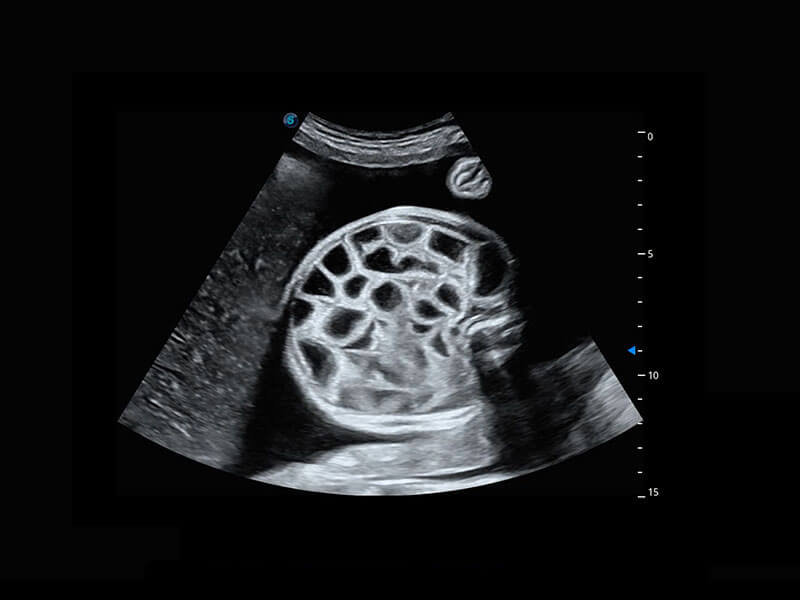

• 新生儿脊髓圆锥

• 新生儿心脏